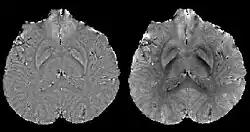

COSMOS solves the inverse problem by oversampling from multiple orientations.[11][12] COSMOS utilizes the fact that the zero cone surface in the Fourier domain is fixed at the magic angle with respect to the B0 field. Therefore, if an object is rotated with respect to the B0 field, then in the object's frame, the B0 field is rotated and thus the cone. Consequently, data that cannot be calculated due to the cone becomes available at the new orientations.

COSMOS assumes a model-free susceptibility distribution and keeps full fidelity to the measured data. This method has been validated extensively in in vitro, ex vivo and phantom experiments. Quantitative susceptibility maps obtained from in vivo human brain imaging also showed high degree of agreement with previous knowledge about brain anatomy. Three orientations are generally required for COSMOS, limiting the practicality for clinical applications. However, it may serve as a reference standard when available for calibrating other techniques.